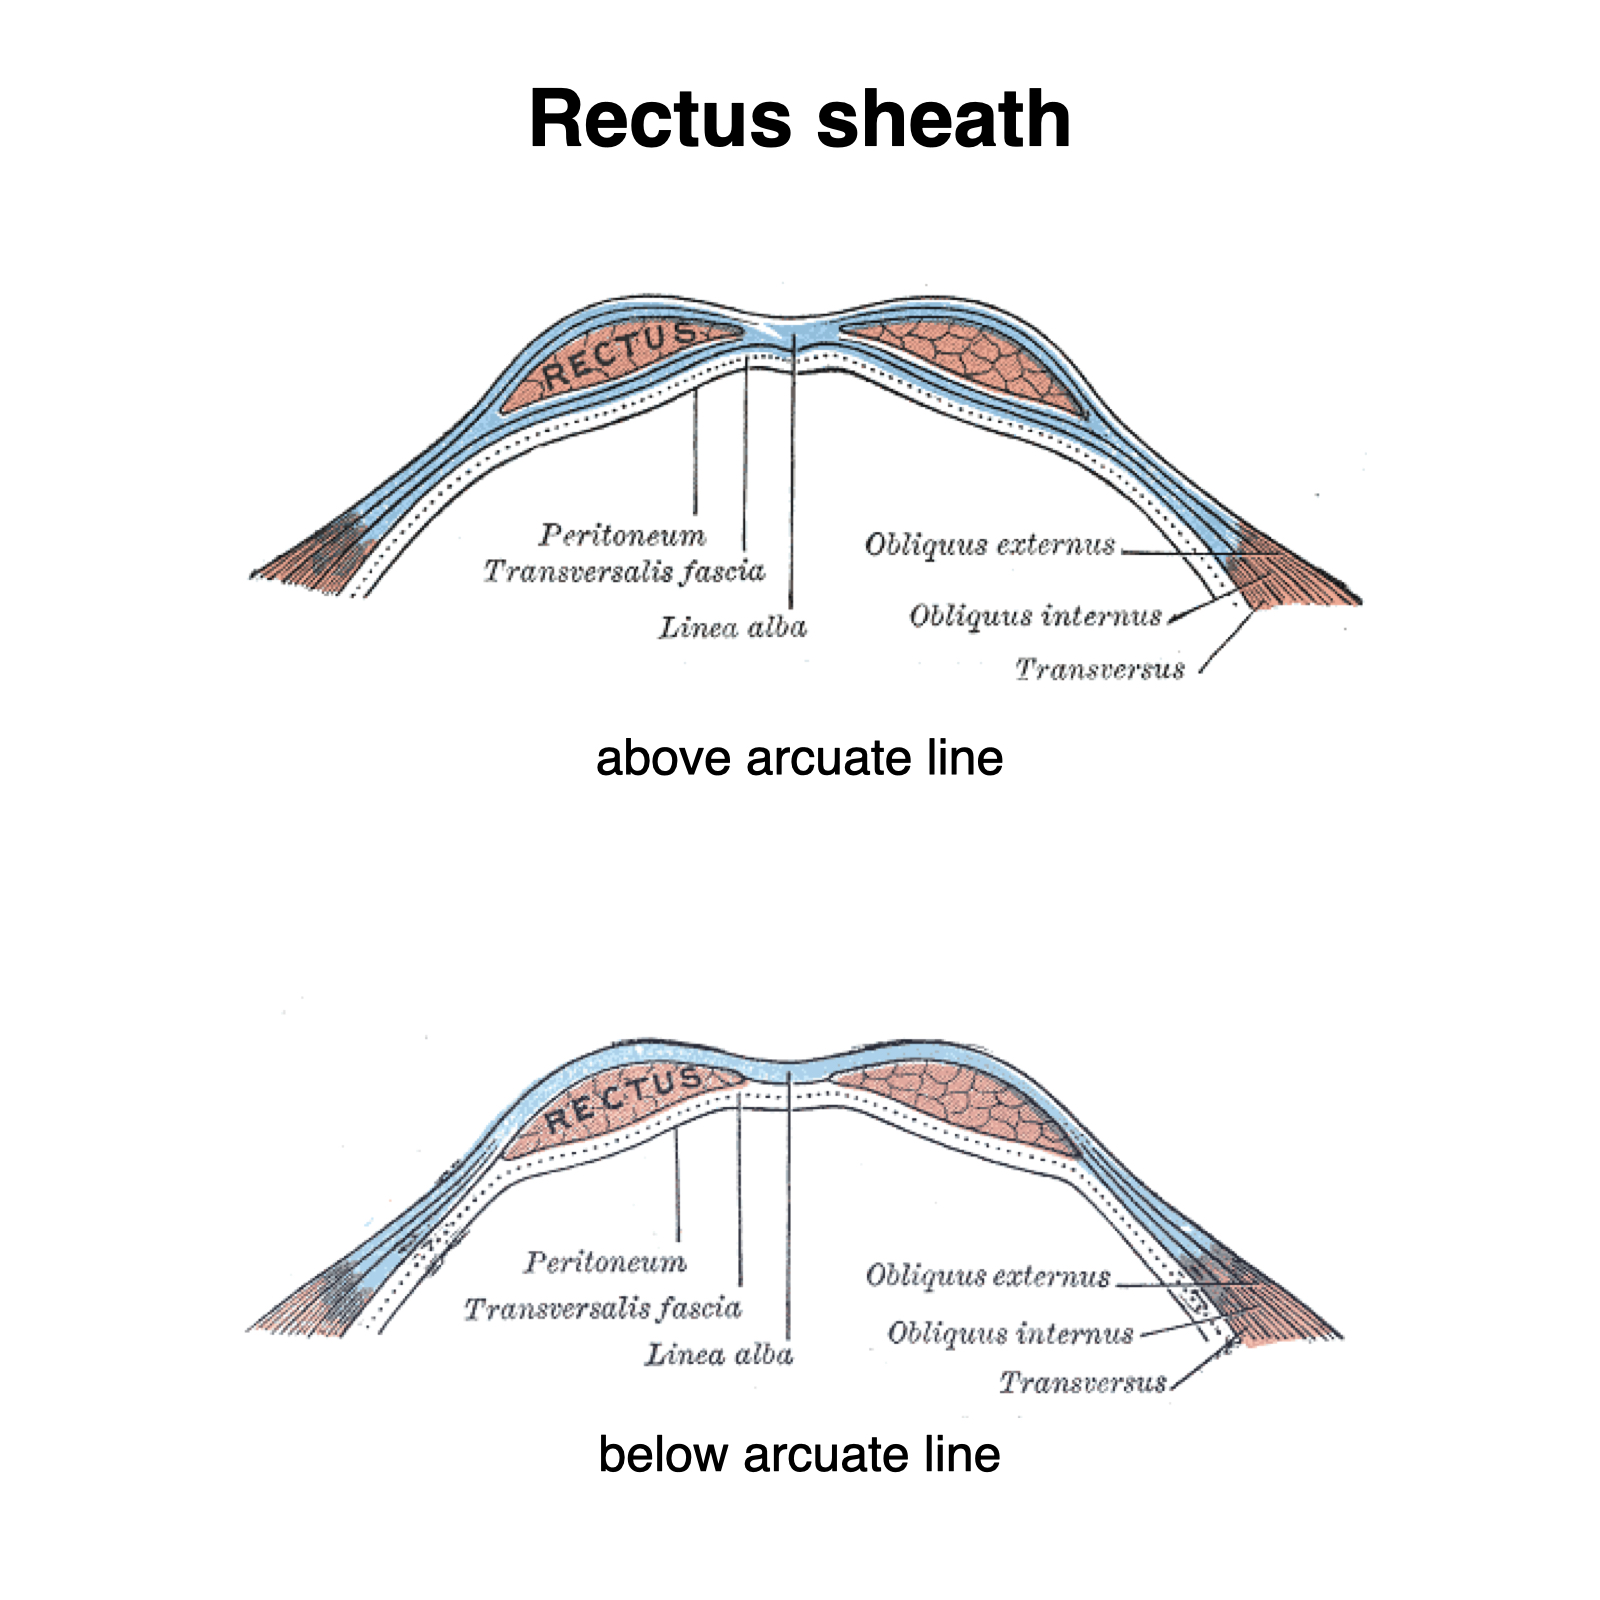

Rectus Sheath

- Components:

- Rectus abdominis with tendinous intersections

- Linea alba (interlacing fibers forming the rectus sheath)

- Semilunar line

- Arcuate line (notable absence of transversus abdominis aponeurosis inferiorly)

*Note from an M2: You will be tested on these lines. Know which differences occur below and above these lines.